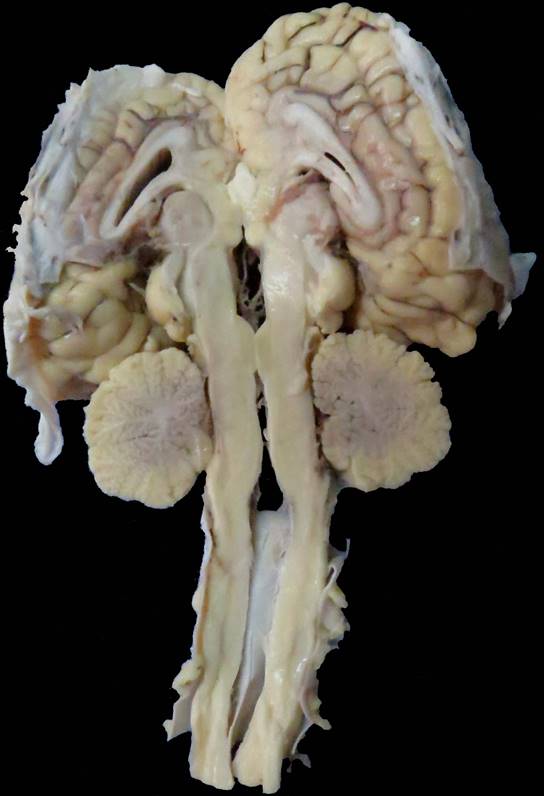

Se utilizaron muestras de diferentes regiones cerebelosas (vermis, hemisferios laterales y lóbulo floculonodular) de una perra american staffordshire terrier de 6 años, que presentaba temblores, debilidad y ataxia como signos clínicos principales en el momento de la primera visita al Centro Hospital Veterinario de la Facultad de Veterinaria de la Universidad de la República (CHV, FVET-Udelar, Montevideo, Uruguay). Los signos neurológicos progresaron durante 6 meses y, debido al mal pronóstico, se realizó la eutanasia con autorización del propietario siguiendo el protocolo de eutanasia del CHV, FVET-Udelar, aprobado por la Comisión de Ética en el Uso de Animales (CEUA, FVET-Udelar) (Verdes et al., 2020). También se estudiaron muestras de las mismas regiones cerebelosas de un caso de AC en un potrillo raza árabe macho (Gagliardi et al., 2018). En resumen, el potrillo había manifestado signos neurológicos a los 40 días de edad, caracterizados por fasciculaciones en diferentes grupos musculares que fueron agravándose en pocos días, mostraba hiperexcitabilidad, mioclonias de músculos del cuello, hiperextensión, ataxia, incoordinación leve a moderada, temblor exacerbado en el cuello cuando caminaba al paso o se detenía, e hiperreflexia. Dado el rápido empeoramiento progresivo, se realizó la eutanasia según se describe en Gagliardi et al. (2018). En ambos casos se hizo una revisión macroscópica del cerebelo, registrándose fotográficamente los cambios morfológicos, así como el tamaño y distribución de las folias y surcos de ambos cerebelos. En el caso del canino, estos detalles se reportan en Verdes et al. (2020), mientras que en el caso del equino se muestran en las figuras 1 y 2. En ambos casos los cerebelos estaban reducidos de tamaño y, en el caso del equino, como se muestra en la figura 1, no llega a llenar la fosa caudal.

Figura 1: Abiotrofia cortical cerebelosa, equino, árabe, 40 días. El cerebelo no llega a llenar la fosa caudal. Nótese la demarcación de los espacios interfoliares que aparecen como surcos más profundos por la retracción de las folias cerebelosas.

Figura 2: Abiotrofia cortical cerebelosa, equino, árabe, 40 días. Detalle del corte sagital del cerebelo que muestra su retracción.